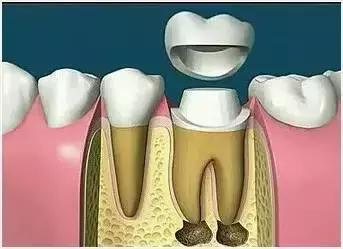

7、根管打桩

因牙体缺损过多,导致牙的强度(承受力量的性能)大幅度下降,不能很好地承受咀嚼力量。打桩的目的是增加牙根及牙冠的强度,增加患牙的稳固。

8、完成牙体修复

X光片显示根管充填完好,可进行暂时或永久牙体修复,带上牙冠,保护患牙。至此根管治疗才可算完成,同时根管治疗后还需复诊,一般周期可为3个月、半年、1年、2年或更长。